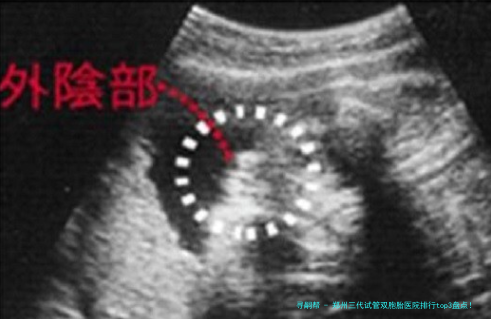

很多人好奇:三代试管真正能""孪生儿吗?谜底是:可以科学方案,但不行确保!关键在于胚胎筛选和移植策略。

双胚胎移植:一次移植两个优质胚胎,增加双胎概率

胚胎体外培养:将胚胎培育至第五日至六日,检查筛选具发育潜能的胚胎